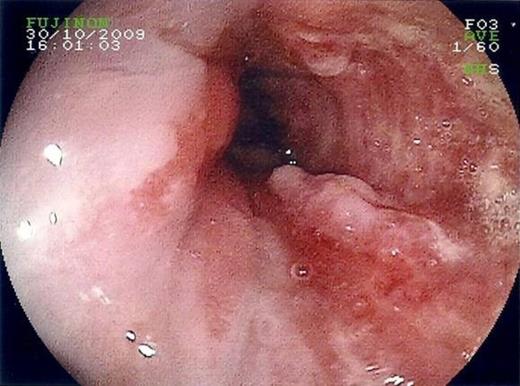

A sixty-one year old man presented with a history of progressive dysphagia, vomiting, weight loss and new onset of back pain. Upper gastrointestinal endoscopy revealed a lesion at the gastro-oesophageal junction (figure 1) and biopsies confirmed the presence of adenocarcinoma with signet ring differentiation. Despite the absence of metastatic disease on computed tomography, positron emission tomography demonstrated multiple vertebral and sternal deposits.